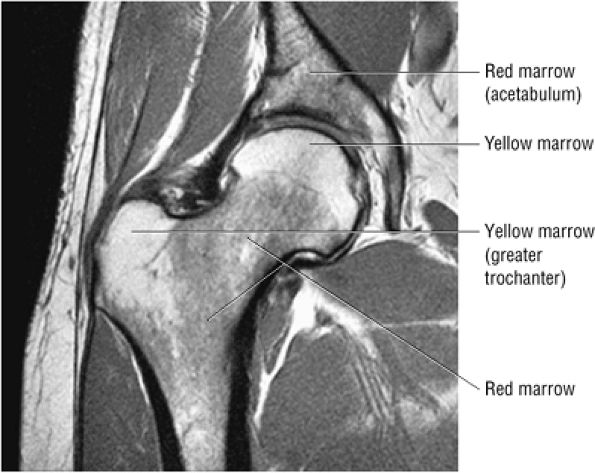

Inhomogeneity of marrow signal intensity in the acetabulum, ilium, and ischium is a normal finding on T1-weighted images, representing normal red and yellow marrow inhomogeneity.

FIGURE 3.72 ● Coronal PD FSE image showing the normal distribution of yellow marrow fat signal intensity in the greater trochanter and femoral epiphysis. In the femoral neck and proximal femoral diaphysis, red marrow is seen with intermediate or lower in signal intensity.